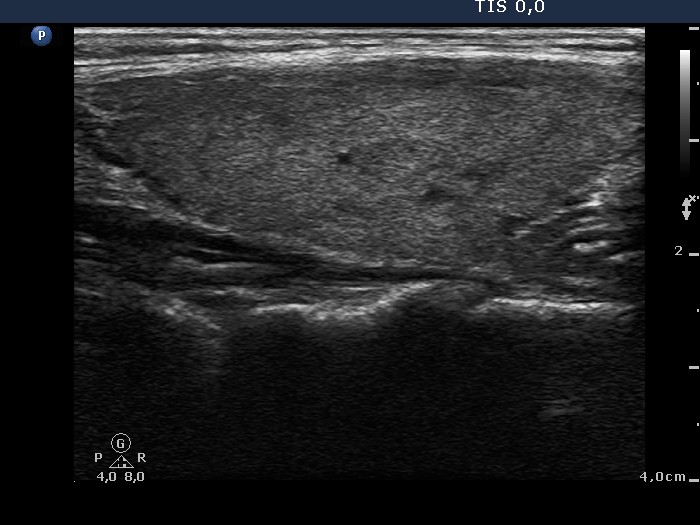

Graves' disease - Case 1049

Follow-up investigation 36 months after first visit (ultrasonographic picture 5)

Patient on daily 10 mg methimazole therapy in euthyroid state

Left lobe, longitudinal scan.